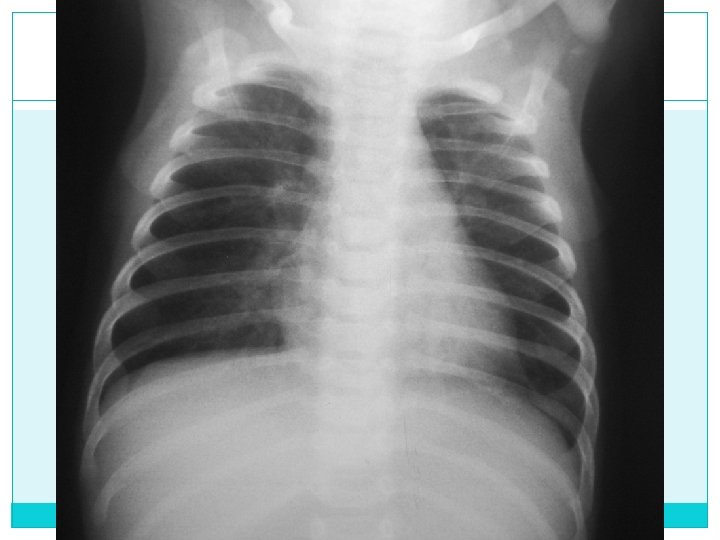

Bien penetrada

Bien Inspirada